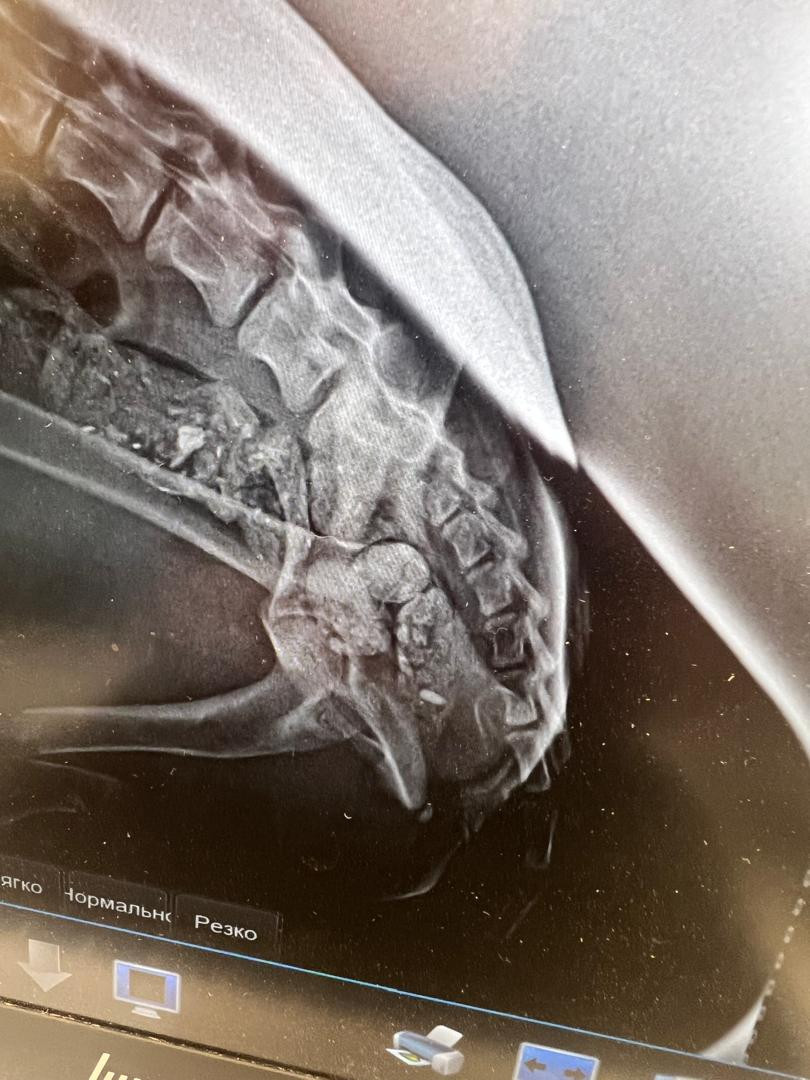

Doctors at the Osh State University Veterinary Clinic have successfully performed osteosynthesis surgery on a dog with fractures in both hind legs for the first time.

Osteosynthesis is a surgical method for fixing broken bones using special metal plates and screws, ensuring proper alignment and rapid healing.

The uniqueness of this operation lies in the fact that osteosynthesis was performed on both hind limbs of the animal—a complex procedure that requires high professionalism, modern surgical equipment, and strict sterile conditions.

During the surgery, the veterinary team carefully aligned the broken bones into the correct anatomical position and secured them with metal plates. This approach significantly reduces the rehabilitation period compared to traditional treatments such as plaster casting or splinting.